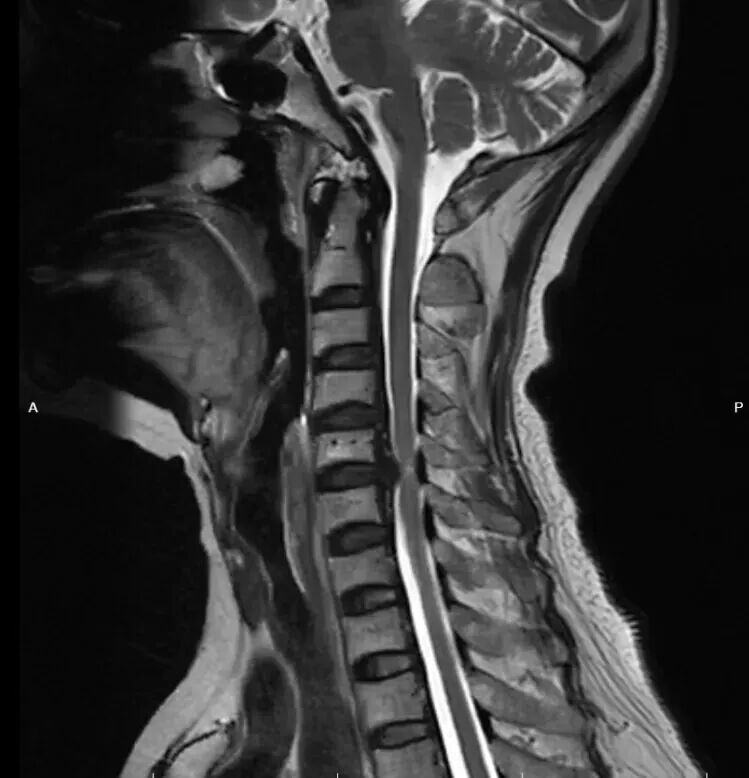

患者李女士,68岁,反复颈部疼痛并四肢麻木3月,影像学检查后确诊为脊髓型颈椎病,C5/6椎间盘突出伴颈髓损伤,保守治疗无效。脊柱外科钟炯彪主任根据患者病情制个体化治疗方案,由于C5/6椎间盘突出部位已出现钙化并有可能与硬膜粘连,手术难度骤增,因此脊柱外科决定采用3D外视显微镜辅助对该患者实施颈椎ACDF术。

术前影像-MRI/CT